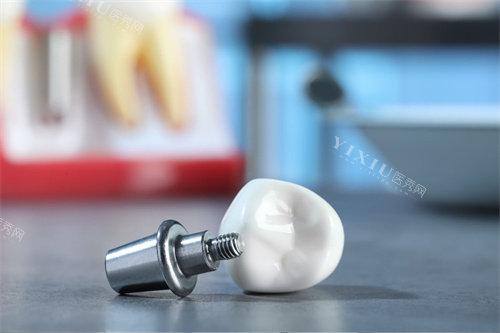

华普兰种植体在国产种植体产品线中属于中高端档次。该产品采用SLA和AOT双功能化表面改性技术,这种技术结合了亲水与疏水特性,能够有效增强骨结合能力。同时,这种表面处理技术还具有抑制细菌附着的功能,有助于降低种植体周围炎的发生风险。在结构设计方面,华普兰种植体的11度莫氏锥度连接设计和斜肩台结构为其稳定性和美学结果提供了因素。

从临床应用角度看,华普兰种植体适合骨量中等或较好的患者群体。在复杂病例处理方面,如骨量不足的情况或穿颧/穿翼手术中,该种植体表现出一定的适应优势。产品设计考虑了与多种手术工具的配套使用需求,支持医生根据患者具体情况制定个性化治疗方案。这种灵活性和适应性使其在临床应用中具备较好的操作性。